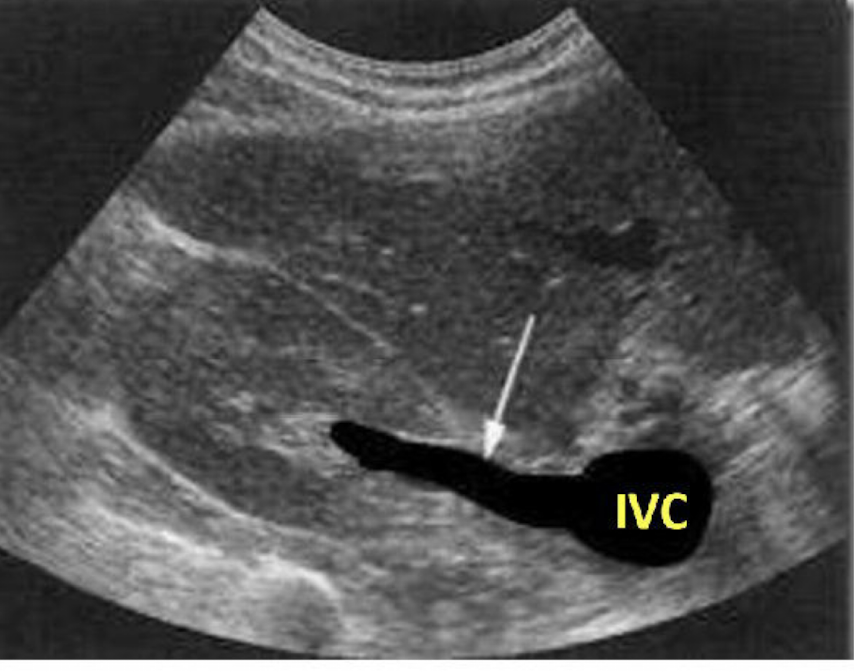

What is this picture showing?

The right renal vein draining into the IVC